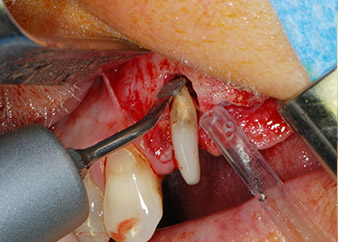

След това апексът се изпилява със същия инструмент, за да се отстрани остатъчната инфектирана апикална тъкан и да се намали възможното допълнително усложнение по кореновите канали (апикоектомия) (Фиг. 5). Ретроградно запълване не е необходимо, защото ортоградното запълване току-що е ревизиран.

букален апекс на зъб 24

Фиг 5: ... и букалният апекс на зъб 24 е обработен със същия инструмент (апикоектомия).